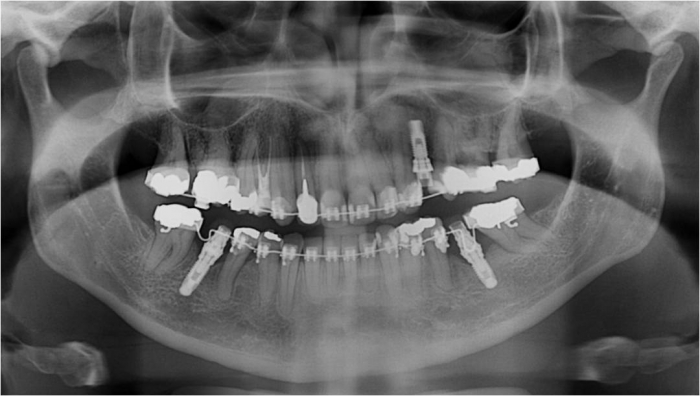

Raio x panorâmico final